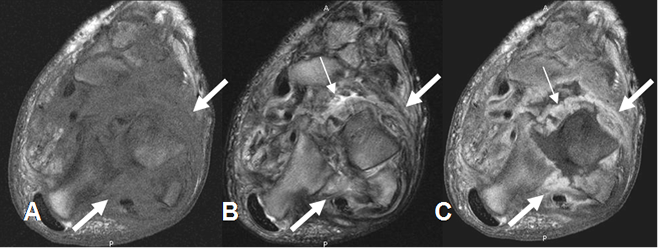

Fig 47. Artropatía neuropática. Patrón atrófico.

A: RM axial en T1, B: RM axial en T2 y C: RM axial en T1 con contraste. Subluxación articular, con cambios inflamatorios de los tejidos blandos, hipointensos en T2 y que realzan con el contraste. (Flechas gruesas). Además hay signos de sinovitis. (Flechas delgadas).